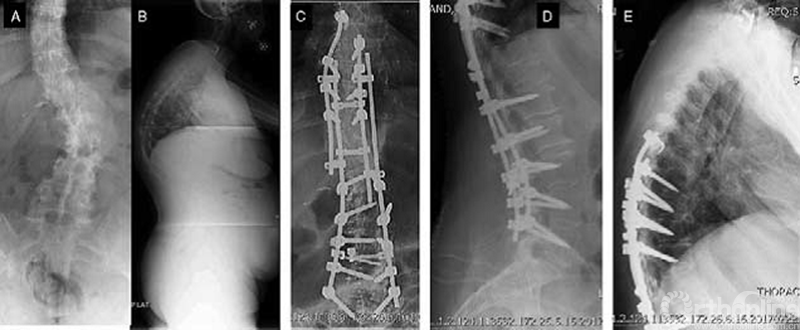

56岁女性,下胸椎后凸和腰椎侧凸。后凸顶点位于下位胸椎(A,B),需行胸段PSO(D),但脊柱侧弯的顶点位于中部腰椎,需行多节段PCO矫正。这两种畸形需分别纠正。采用棒与棒多米诺连接完成一期手术内固定(C,D,E)。